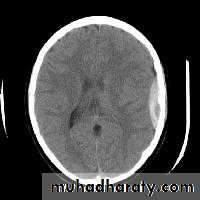

ACUTE INFARCTION

* wedge shape hypo density area.* Shifting of the midline & frontal horn